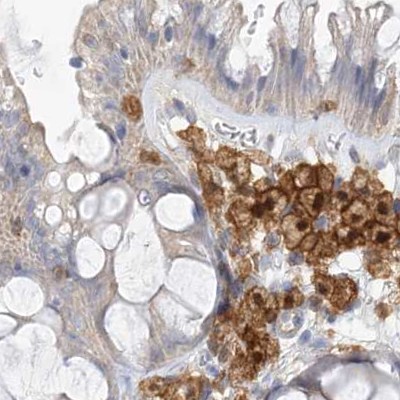

Immunohistochemical staining of human colon, kidney, liver and tonsil using Anti-NAGK antibody HPA035206 (A) shows similar protein distribution across tissues to independent antibody HPA035207 (B).